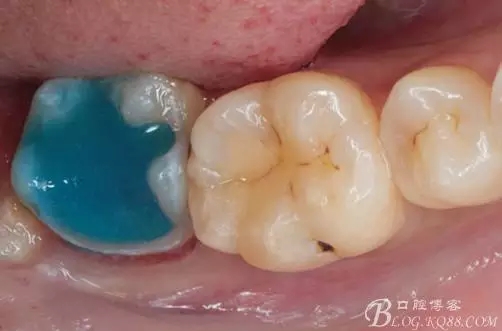

一周后復診,37臨時充填物完好。去除臨時充填物,清潔基牙,試戴嵌體,就位良好,邊緣密合。取下嵌體,常規(guī)處理,9.5%HF處理20S,沖洗一分鐘,95%酒精蕩洗5分鐘?;劳磕?7%的磷酸凝膠,釉質(zhì)區(qū)域酸蝕30S,本質(zhì)區(qū)域15S。粘固用的是3M第八代粘接劑套裝,照說明書逐步操作。最終固化時涂滿阻氧劑,每個牙面最少光照30S,光固化燈用漸強模式。常規(guī)調(diào)合,配合硅膠尖套裝拋光。術后常規(guī)醫(yī)囑,不適隨診。

④嵌體顏色與基牙的差異也是一遺憾。